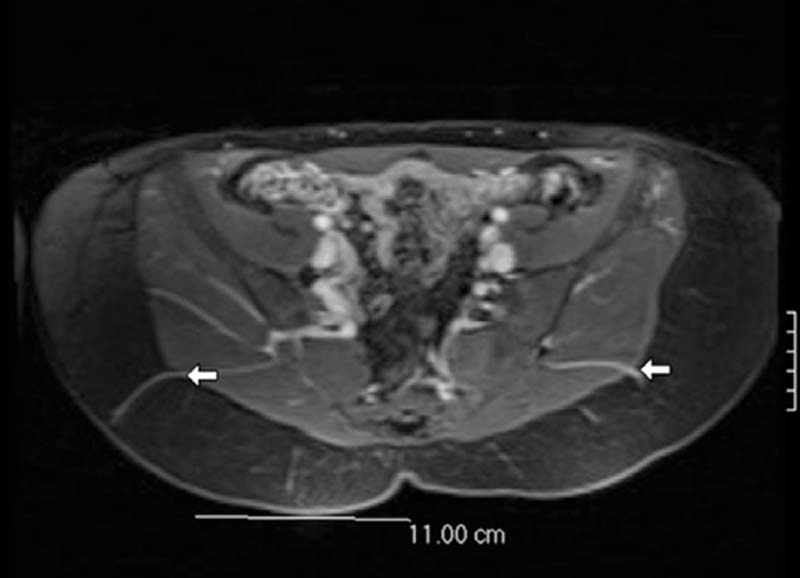

Two microsurgeons who are experienced with perforator techniques and principles work together on each case. The primary surgeon meets with the patient the day before surgery at the presurgery planning appointment. At this time surgical markings are placed based on a review of the magnetic resonance angiogram (MRA) and the use of the handheld Doppler. Preoperative imaging with an MRA or a computed tomography angiogram (CTA) greatly enhances the application of the gluteal donor site and the perforator flap concept. Imaging combined with a handheld Doppler exam enables more detailed tailoring of the flap and is particularly helpful for bilateral simultaneous GAP (BSG) flap harvesting.

During the presurgery marking, the MRA is reviewed in detail.1 The location of the largest GAPs are described by the radiologist using a coordinate system. Each large perforator is measured from a midline reference point on the patient’s skin. The reference point is the top of the gluteal crease or tip of the coccyx. The radiologist records the horizontal distance and the vertical distance from the reference point. The perforator location is measured at the point it leaves the muscle, and the location is extrapolated to the position on the skin where the Doppler signal will be heard. It is important to note that the both the MRA and markings are performed with the patient in the prone position.

The images are reviewed, and the best perforators are chosen with regard to size, location, distribution of fat around the perforator, and the intramuscular/submuscular course of each vessel. For a bilateral case, note is made of the most symmetrical pair of perforators on the right and left side ( Fig. 6.2 ). There are two important points to note: (1) whether a perforator is located in the medial or lateral third of the flap, and (2) whether there is a septocutaneous (sc) GAP between the gluteus maximus and medius muscles.2 The more lateral perforators and sc-GAP will have a more tangential course around the gluteus maximus muscle and result in a longer pedicle, which is preferred. The medial perforators will have a more direct intramuscular course and shorter pedicle. Perforator selection is important for symmetry and for exposure during the microsurgical anastomosis.